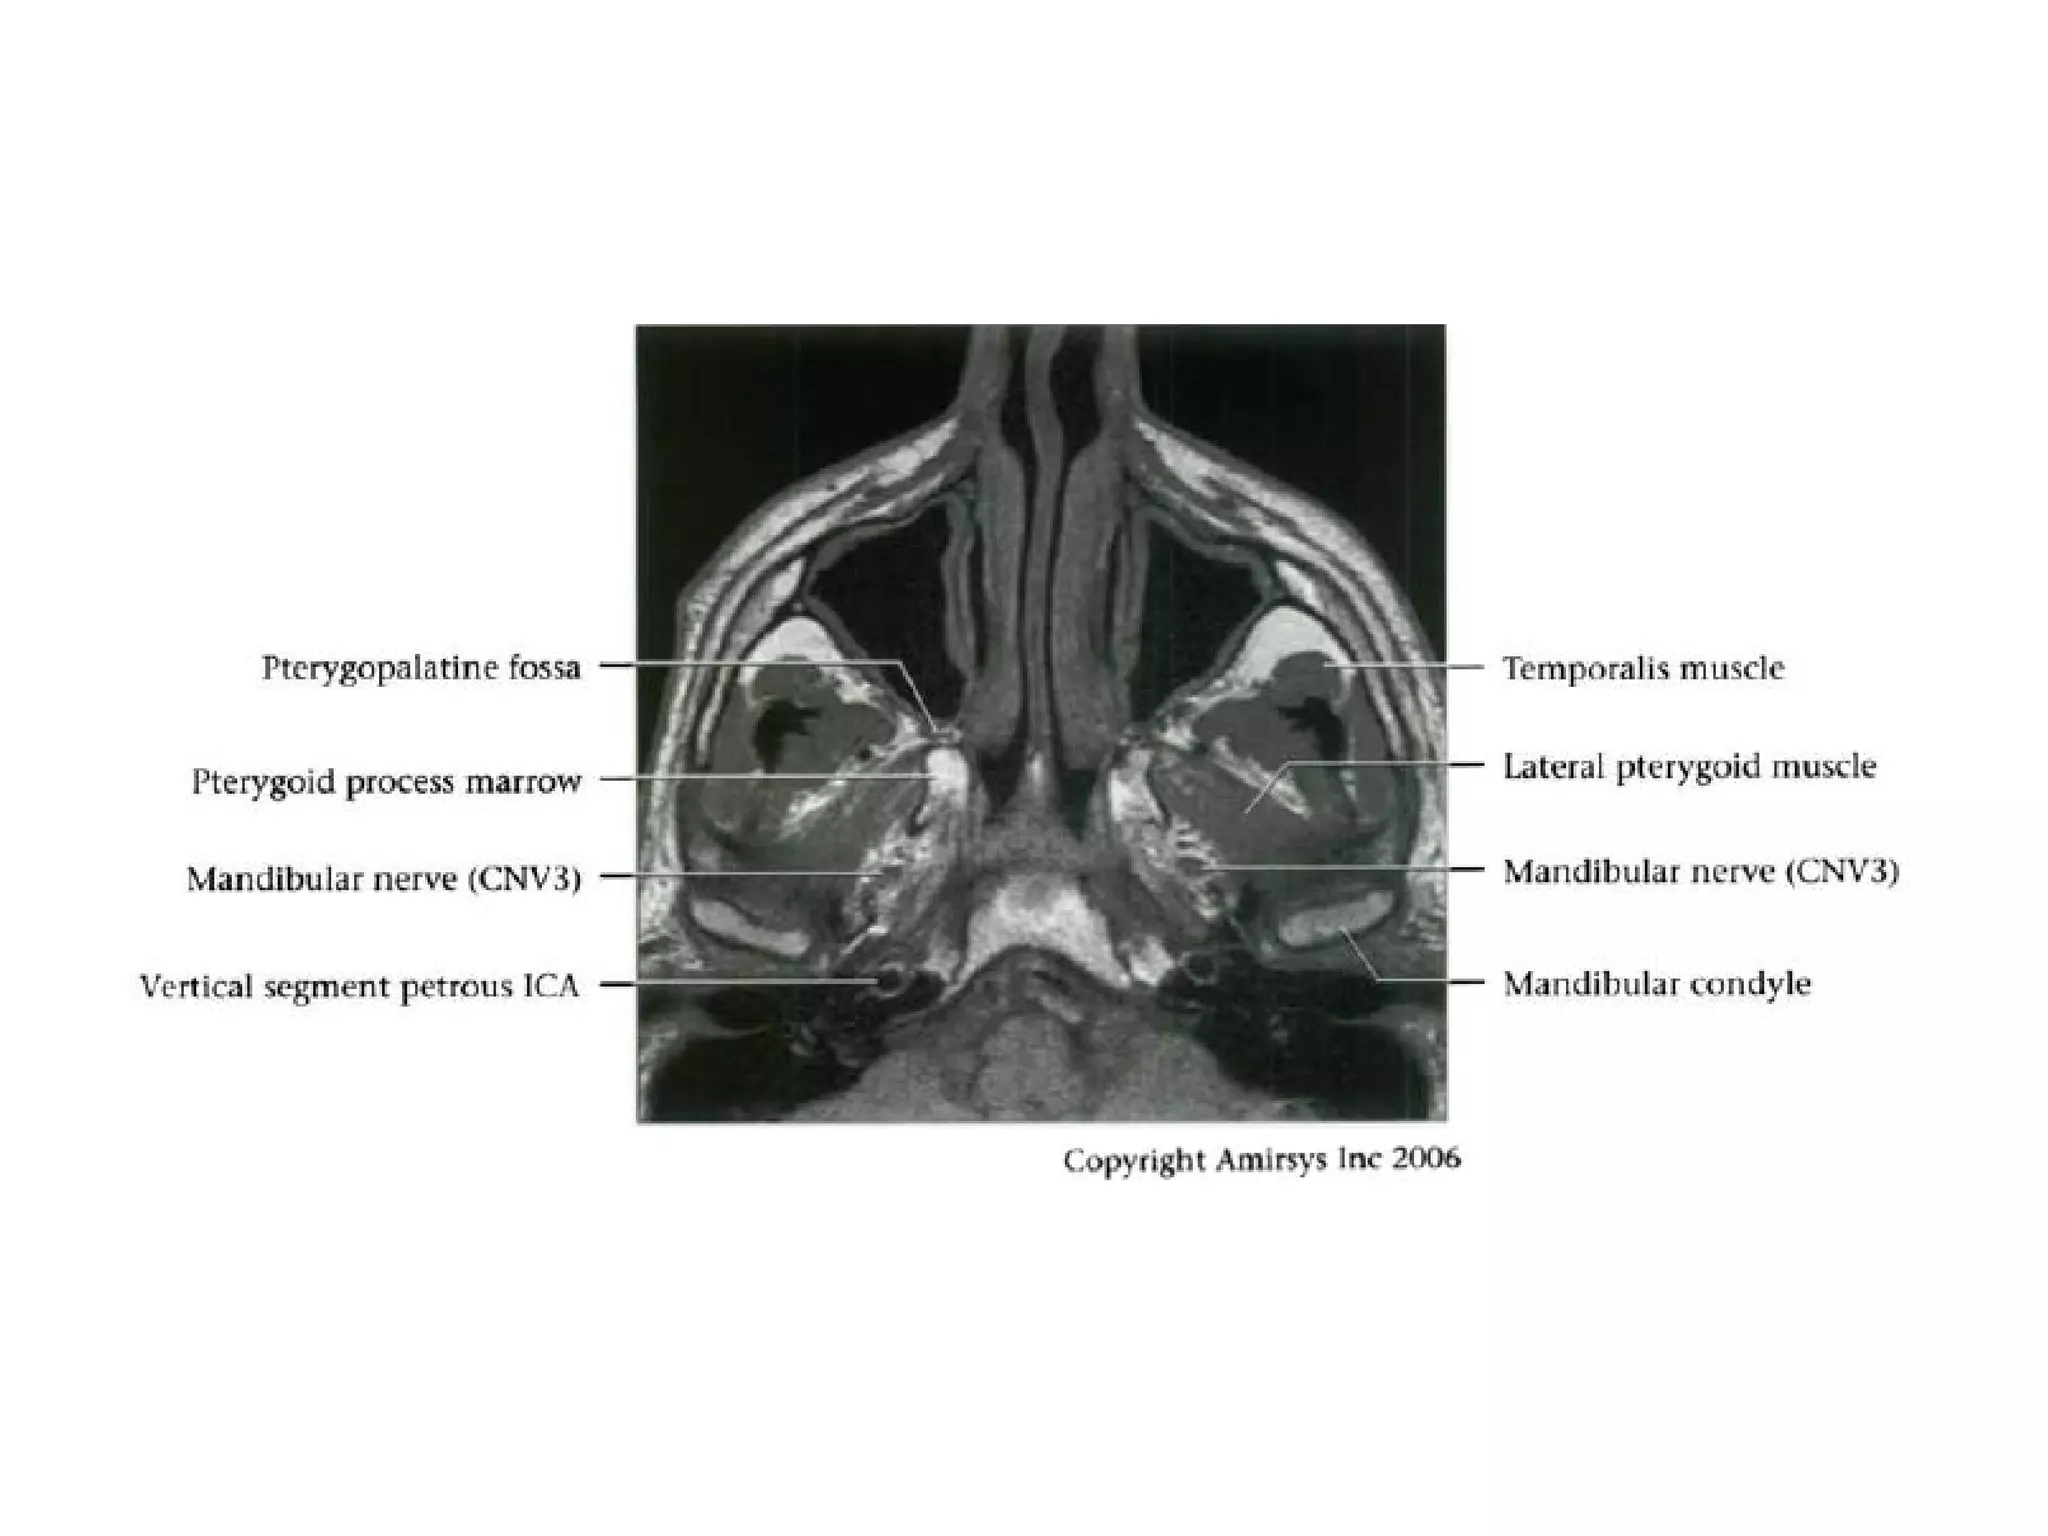

Cranial Nerve V:

The Trigeminal Nerve

• The trigeminal nerve is the largest cranial nerve.

• It is composed of a large sensory root that

runs medial to a smaller motor root.

• The roots emerge from the lateral midpons and

travel anteriorly through the prepontine cistern

and the porus trigeminus to the Meckel

(trigeminal) cave, a CSF-containing pouch in the

middle cranial fossa.

• In the Meckel cave, the nerve forms a meshlike web that

can be visualized only with high-resolution imaging.

• Along the anterior aspect of the cavity, the trigeminal

nerve forms the trigeminal (gasserian) ganglion before

splitting into three subdivisions.

• The ophthalmic (V1) and maxillary (V2) divisions of the

nerve move medially into the cavernous sinus and exit

the skull through the superior orbital fissure and foramen

rotundum, respectively.

• The mandibular division (V3), which includes the motor

branches, exits the skull inferiorly through the foramen

ovale.

RadioGraphics 2009; 29:1045–1055